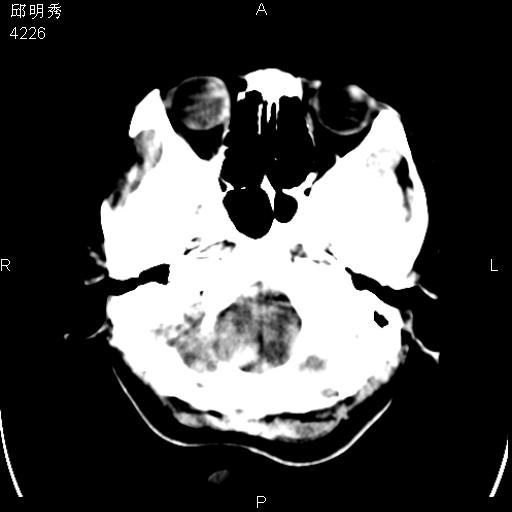

40f头晕十多天,右上肢麻木一天

脑白质变性或ms

脑白质脱髓鞘改变。

脑白质病;建议行mri检查。